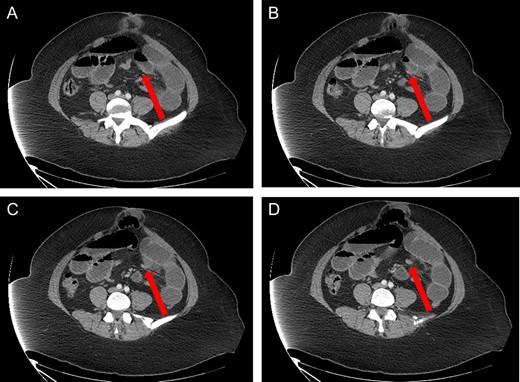

A 40-year-old woman presented to the emergency department with abdominal pain for 4 days. She had previously been seen at an outside hospital 3 days earlier, and was diagnosed with biliary colic. Her pain was constant, and was associated with nausea and vomiting. She had a history of a cesarean section, but no other abdominal surgeries. Her vitals were within normal limits: afebrile at 36.9°C, heart rate 71 beats/minute, blood pressure 143/62 mmHg, respiratory rate 18 breaths/minute, and oxygen saturation 97% on room air. On abdominal exam, she was distended, tender, demonstrated voluntary guarding and was positive for peritonitis. Laboratory values were significant for a white blood cell count of 16.1 K/ul, with 80.2% neutrophils, hemoglobin 14.9 g/dl, hematocrit 45.4%, platelets 349 K/ul and lactic acid 0.9 mEq/L; her chemistry was unremarkable. A computed-tomography (CT) scan of the abdomen and pelvis that was obtained prior to surgical consultation demonstrated the proximal two-thirds of small bowel dilated up to 4 cm, with a sharp transition point in the left mid-abdomen, and collapsed small bowel loops near the cecum. The colon was mostly collapsed. A few distended loops bulged into a paraumbilical hernia, which was 6 cm wide and not the cause of obstruction (Figs 1–3).

Coronal view: arrow pointing to the sharp transition point, where the distal end of the closed loop small bowel herniated through a hole in the sigmoid epiploica, demonstrating collapsed small bowel distally.

Axial view: (A) and (B) arrows pointing to dilated small bowel from the closed loop obstruction. (C) and (D) arrows pointing to the transition point, where the small bowel is collapsed distally.